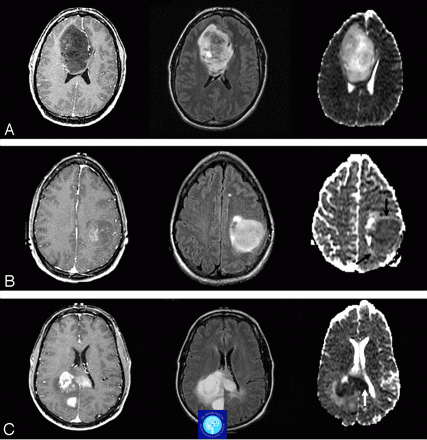

تشخیص دقیق تومور مغزی گام اول درمان است. ابتدا معاینه بالینی و نورولوژیک انجام میشود تا علائم ارزیابی شود. سپس، تصویربرداری مانند MRI (تصویربرداری رزونانس مغناطیسی) که بهترین روش برای شناسایی اندازه و مکان تومور است، یا CT اسکن برای موارد اورژانسی استفاده میشود. در نهایت، بیوپسی (نمونهبرداری از بافت تومور) برای تعیین نوع دقیق تومور ضروری است. این روشها در مراکز شیراز مانند بیمارستانهای دانشگاهی موجود هستند و به بهترین جراح تومور مغزی کمک میکنند برنامه درمانی بچیند.

روشهای جراحی تومور مغزی – MRI تومور مغزی